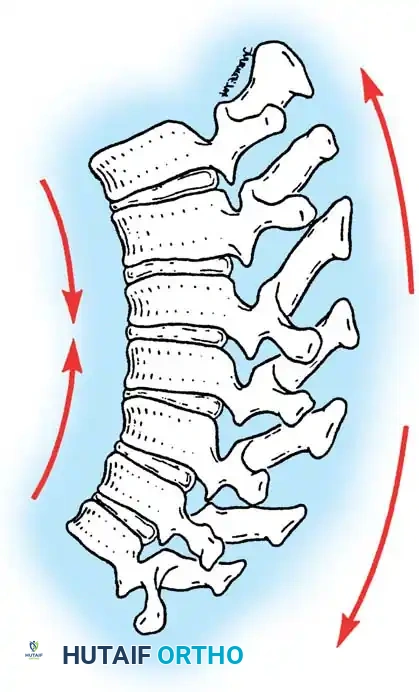

Kyphosis measuring 50 degrees or more in the thoracic spine is generally considered abnormal. Pathologic kyphotic deformity typically manifests when the anterior spinal column is unable to withstand compressive loads, leading to anterior column shortening. Conversely, disruption of the posterior column and an inability to resist tensile forces can lead to relative lengthening of the posterior elements, further exacerbating the kyphosis.

Clinical Pearl: The fundamental biomechanical principle of kyphotic deformity is the failure of the anterior column under compression combined with the failure of the posterior column under tension. Surgical correction must address both vectors: anterior column support and posterior column shortening.

2. Facetectomies and Ponte Osteotomies

To mobilize the rigid deformity, wide, bilateral, multi-level Ponte osteotomies are performed at the apex of the curve.

* The inferior articular processes of the cranial vertebra and the superior articular processes of the caudal vertebra are resected.

* The ligamentum flavum is completely excised, exposing the dura.

* This posterior column shortening allows for 5 to 10 degrees of correction per level when the spine is extended.

5. Apical Compression

Once the rods are seated, sequential compression is applied across the apical screws. This closes the Ponte osteotomies, shortens the posterior column, and acts as a fulcrum to lengthen the anterior column, effectively reversing the biomechanical pathology of Scheuermann disease.